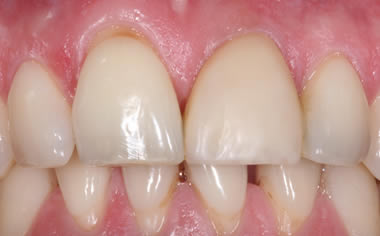

More front teeth replaced by dental implants

Case Three (4 images)